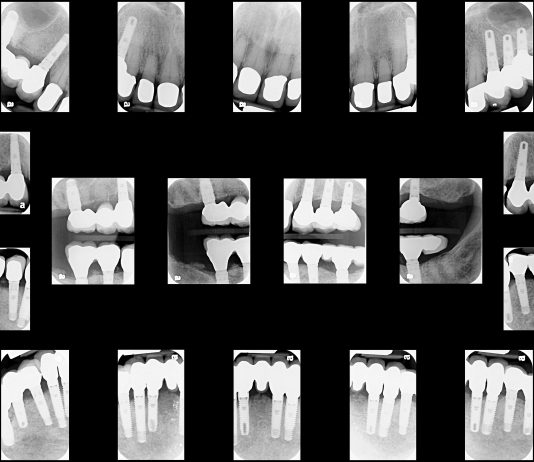

If you are suffering from damaged, decayed or missing teeth, dental implants may be the ideal solution. The implants provide a strong foundation for custom-made replacement teeth that feel and look completely natural, and they are an effective, long-lasting solution for a variety of dental issues. In addition to supporting...